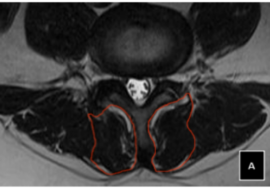

يُعد اعوجاج العمود الفقري مجهول السبب عند المراهقين (Adolescent Idiopathic Scoliosis – AIS) من أكثر اضطرابات العمود الفقري شيوعًا في مرحلة النمو، ويُعتبر العلاج بحزام اعوجاج العمود الفقري (Brace) الطريقة التحفظية الأكثر استخدامًا لتصحيح الانحناء ومنع تفاقمه.

يتم تصميم الحزام بشكل مخصص لكل مريض بناءً على زاوية الاعوجاج (زاوية كوب)، ومكان الانحناء، وسن المريض، ومستوى نمو العظام.

التطور الكبير في تصميم الأحزمة الطبية جعل علاج اعوجاج العمود الفقري عند المراهقين أكثر نجاحًا وأقل إزعاجًا. باستخدام تقنيات التصوير الثلاثي الأبعاد والمحاكاة الرقمية، أصبح الحزام أكثر خفة وراحة، ويعطي نتائج أفضل في تصحيح الانحناء والتواء العمود الفقري.